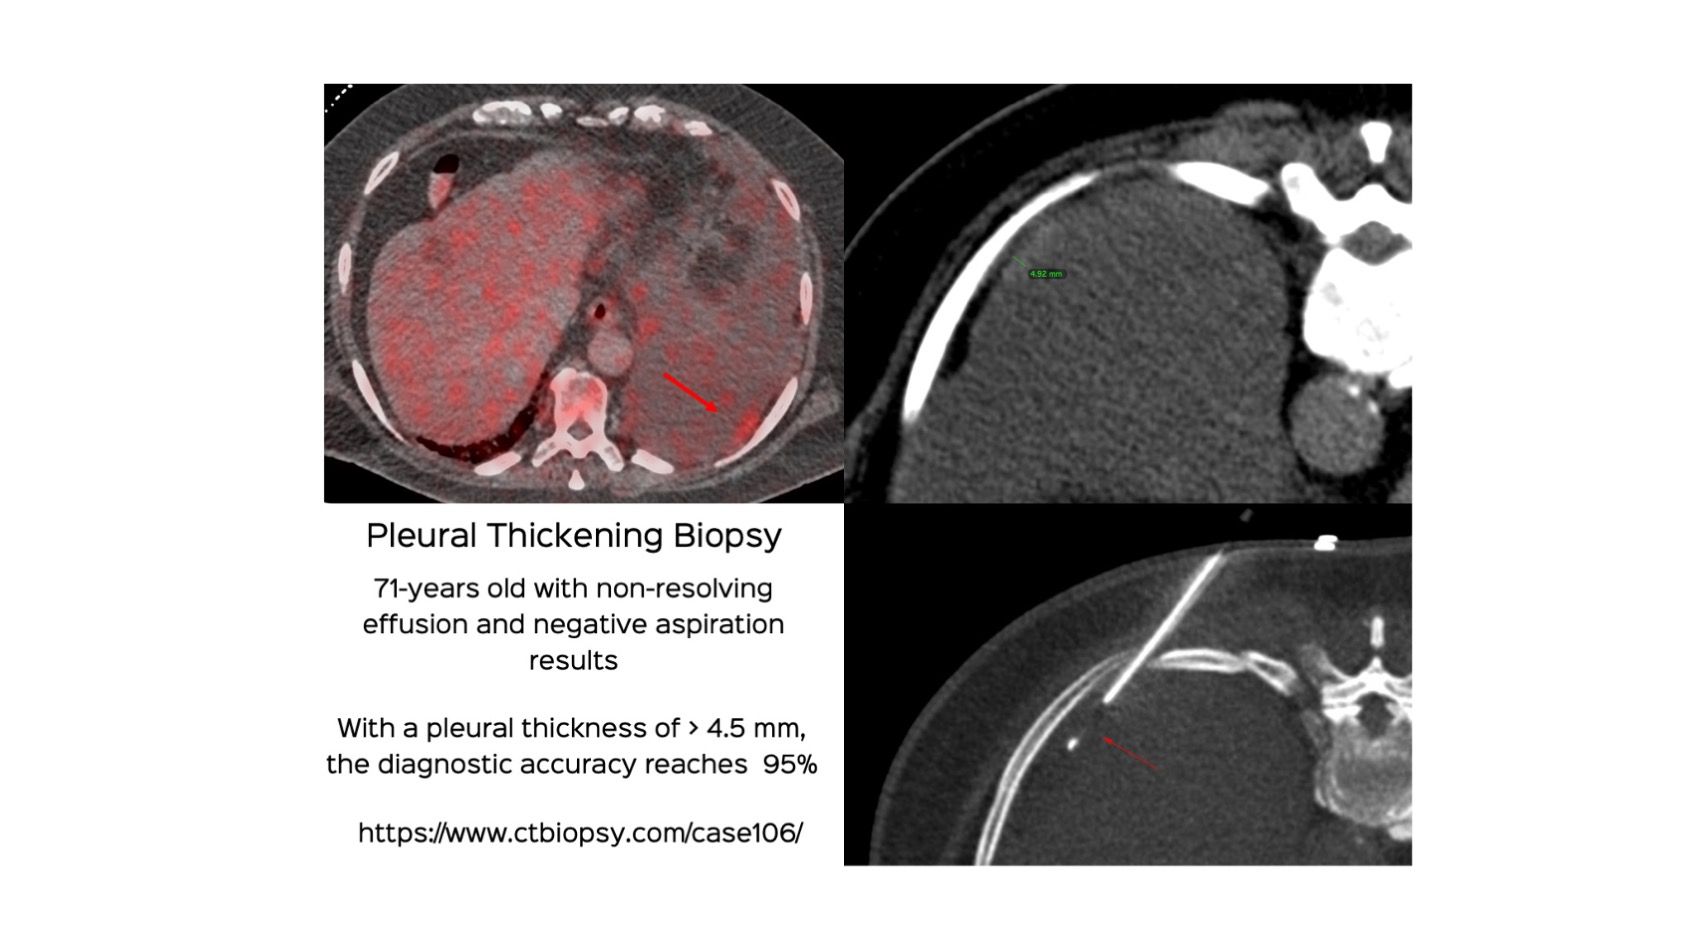

Case 106: Pleural Thickening Biopsy

Bhavin Jankharia - 29 September 2022